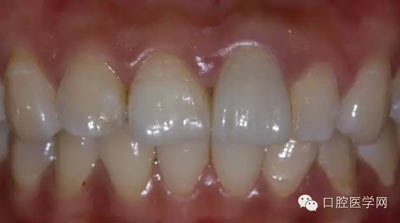

8、術(shù)前術(shù)后對比

6、術(shù)后一周照,牙齦恢復(fù)良好

7、術(shù)后照飽和度調(diào)到最低與最高,觀察牙齒修復(fù)后的明度及飽和度